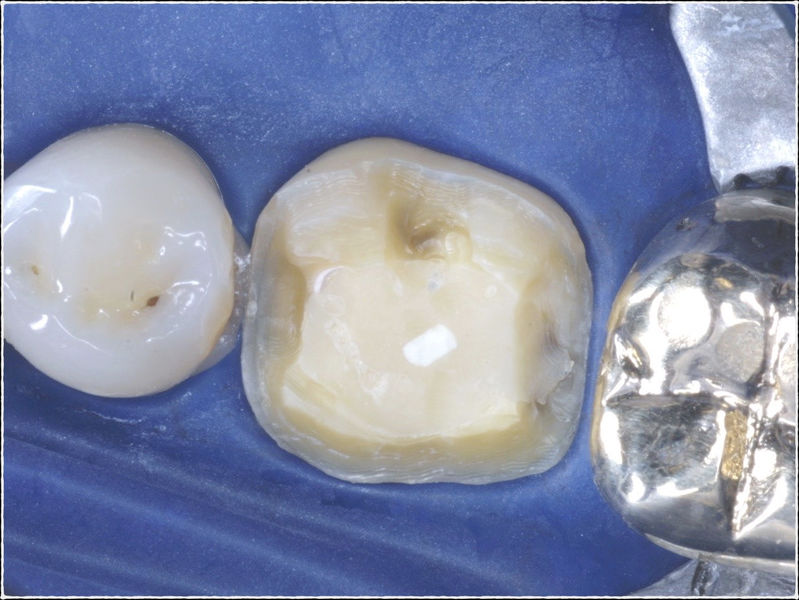

Restauraciones fabricadas en el laboratorio con materiales estéticos, los cuales cubren de manera parcial dientes posteriores. Se utilizan primariamente para restaurar dientes con caries, fracturas y/o defectos amplios. Para poder enviar el caso al laboratorio se toman impresiones utilizando materiales de impresión o técnicas modernas digitales.

Disciplina fundamental de la Odontología enfocada en el diagnóstico, prevención y tratamiento restaurador de las piezas dentales que han sufrido daños. Su objetivo principal es devolver al diente su equilibrio biológico, funcional y estético cuando su integridad ha sido alterada. Resinas directas, incrustaciones, coronas.